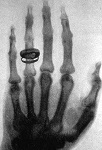

\(\newcommand{\avec}{\mathbf a}\) \(\newcommand{\bvec}{\mathbf b}\) \(\newcommand{\cvec}{\mathbf c}\) \(\newcommand{\dvec}{\mathbf d}\) \(\newcommand{\dtil}{\widetilde{\mathbf d}}\) \(\newcommand{\evec}{\mathbf e}\) \(\newcommand{\fvec}{\mathbf f}\) \(\newcommand{\nvec}{\mathbf n}\) \(\newcommand{\pvec}{\mathbf p}\) \(\newcommand{\qvec}{\mathbf q}\) \(\newcommand{\svec}{\mathbf s}\) \(\newcommand{\tvec}{\mathbf t}\) \(\newcommand{\uvec}{\mathbf u}\) \(\newcommand{\vvec}{\mathbf v}\) \(\newcommand{\wvec}{\mathbf w}\) \(\newcommand{\xvec}{\mathbf x}\) \(\newcommand{\yvec}{\mathbf y}\) \(\newcommand{\zvec}{\mathbf z}\) \(\newcommand{\rvec}{\mathbf r}\) \(\newcommand{\mvec}{\mathbf m}\) \(\newcommand{\zerovec}{\mathbf 0}\) \(\newcommand{\onevec}{\mathbf 1}\) \(\newcommand{\real}{\mathbb R}\) \(\newcommand{\twovec}[2]{\left[\begin{array}{r}#1 \\ #2 \end{array}\right]}\) \(\newcommand{\ctwovec}[2]{\left[\begin{array}{c}#1 \\ #2 \end{array}\right]}\) \(\newcommand{\threevec}[3]{\left[\begin{array}{r}#1 \\ #2 \\ #3 \end{array}\right]}\) \(\newcommand{\cthreevec}[3]{\left[\begin{array}{c}#1 \\ #2 \\ #3 \end{array}\right]}\) \(\newcommand{\fourvec}[4]{\left[\begin{array}{r}#1 \\ #2 \\ #3 \\ #4 \end{array}\right]}\) \(\newcommand{\cfourvec}[4]{\left[\begin{array}{c}#1 \\ #2 \\ #3 \\ #4 \end{array}\right]}\) \(\newcommand{\fivevec}[5]{\left[\begin{array}{r}#1 \\ #2 \\ #3 \\ #4 \\ #5 \\ \end{array}\right]}\) \(\newcommand{\cfivevec}[5]{\left[\begin{array}{c}#1 \\ #2 \\ #3 \\ #4 \\ #5 \\ \end{array}\right]}\) \(\newcommand{\mattwo}[4]{\left[\begin{array}{rr}#1 \amp #2 \\ #3 \amp #4 \\ \end{array}\right]}\) \(\newcommand{\laspan}[1]{\text{Span}\{#1\}}\) \(\newcommand{\bcal}{\cal B}\) \(\newcommand{\ccal}{\cal C}\) \(\newcommand{\scal}{\cal S}\) \(\newcommand{\wcal}{\cal W}\) \(\newcommand{\ecal}{\cal E}\) \(\newcommand{\coords}[2]{\left\{#1\right\}_{#2}}\) \(\newcommand{\gray}[1]{\color{gray}{#1}}\) \(\newcommand{\lgray}[1]{\color{lightgray}{#1}}\) \(\newcommand{\rank}{\operatorname{rank}}\) \(\newcommand{\row}{\text{Row}}\) \(\newcommand{\col}{\text{Col}}\) \(\renewcommand{\row}{\text{Row}}\) \(\newcommand{\nul}{\text{Nul}}\) \(\newcommand{\var}{\text{Var}}\) \(\newcommand{\corr}{\text{corr}}\) \(\newcommand{\len}[1]{\left|#1\right|}\) \(\newcommand{\bbar}{\overline{\bvec}}\) \(\newcommand{\bhat}{\widehat{\bvec}}\) \(\newcommand{\bperp}{\bvec^\perp}\) \(\newcommand{\xhat}{\widehat{\xvec}}\) \(\newcommand{\vhat}{\widehat{\vvec}}\) \(\newcommand{\uhat}{\widehat{\uvec}}\) \(\newcommand{\what}{\widehat{\wvec}}\) \(\newcommand{\Sighat}{\widehat{\Sigma}}\) \(\newcommand{\lt}{<}\) \(\newcommand{\gt}{>}\) \(\newcommand{\amp}{&}\) \(\definecolor{fillinmathshade}{gray}{0.9}\)Diagnostic Imaging principles and concepts are augmented by the presentation of images for common clinical conditions. Guiding principles related to minimizing radiation exposure and requesting the most appropriate imaging examination are addressed.Static images are enhanced by the ability to access images stored and displayed on an Html-5 compatible, Dicom image viewer that simulates a simple Picture Archive and Communication system (PACS). Users can also access other imaging from the Dicom viewer (ODIN), beyond the basic curriculum provided, to further advance their experience with viewing diagnostic imaging pathologies.